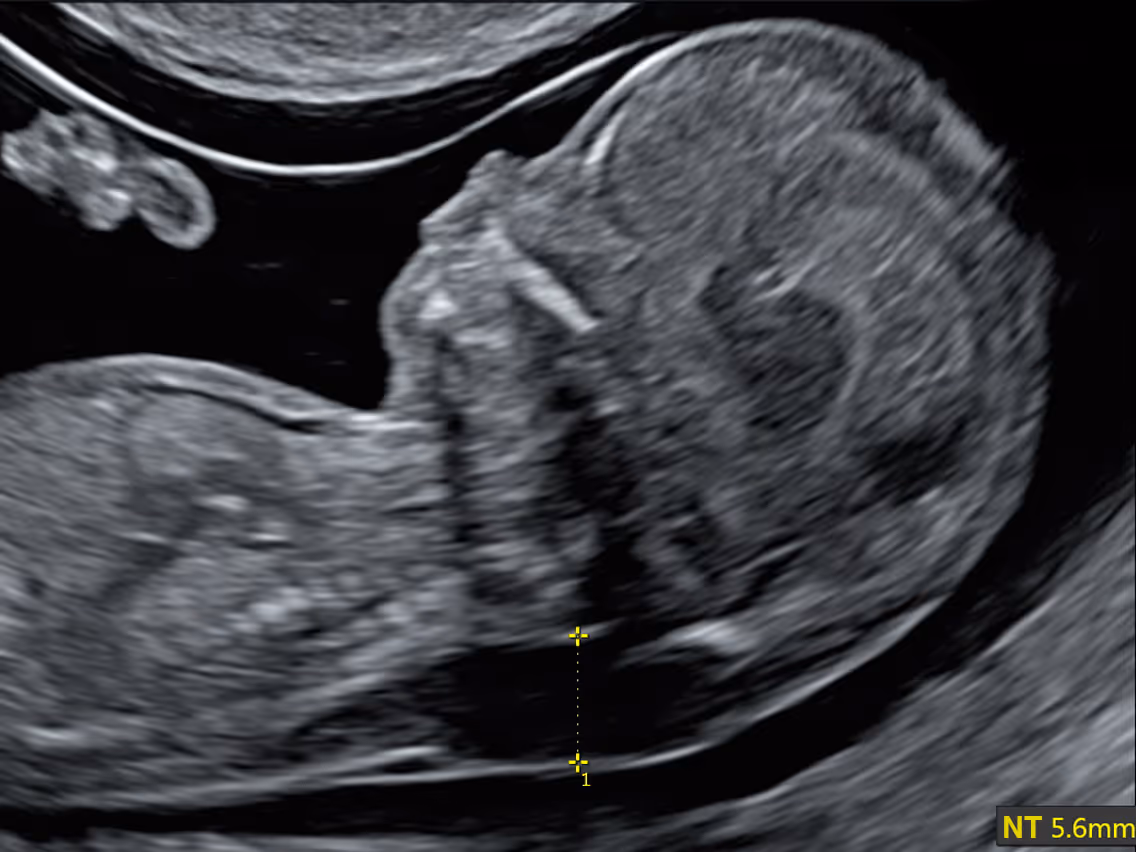

While most studies define increased NT as a measurement above the 95th centile, in clinical practice a fixed cut-off of 3.5 mm is commonly used to define an abnormal NT. This value, corresponding approximately to the 99th centile, has been adopted by the NHS in the UK.

The NT measurement technique was developed by Prof Kypros Nicolaides and the Fetal Medicine Foundation (FMF) in the UK, setting the international standard for accurate and consistent NT assessment. According to the FMF protocol the baby is imaged in a true mid-sagittal plane showing the facial profile. NT is measured as the maximum thickness of the fluid space between the skin and soft tissue over the neck, with the fetus in a neutral position and the image magnified so the head and upper chest fill the screen. Callipers are placed on the inner borders of the echogenic lines defining the NT. To ensure accuracy, three separate measurements are recommended, and the largest valid reading is recorded.

If the NT is equal or above 3.5 mm, the first step is to perform chromosomal testing - either NIPT or a diagnostic test such as CVS or amniocentesis. A specialist ultrasound and fetal echocardiography are then recommended to check for structural and heart abnormalities. Even if results are normal, follow-up scans at 20 weeks and later are advised, as some problems can appear later.